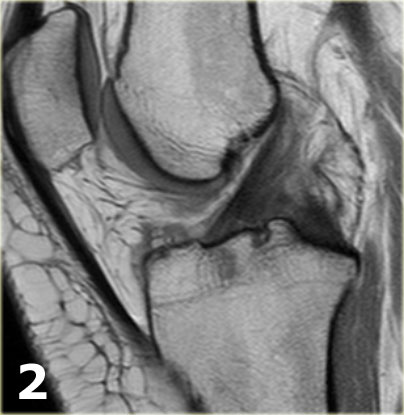

Hãy quan sát hình ảnh bên trái và cố gắng xác định vấn đề của sụn chêm này là gì.

Sau đó tiếp tục xem các hình ảnh liên tiếp tiếp theo của cùng bệnh nhân này.

Như bạn đã đoán được qua tiêu đề của đoạn này, đây là một trường hợp sụn chêm lật (flipped meniscus).

Sụn chêm lật là một dạng đặc biệt của rách dạng quai xô (bucket-handle tear).

Sụn chêm lật xảy ra khi mảnh vỡ của sừng sau bị lật ra phía trước, khiến sừng trước của sụn chêm có vẻ to hơn bình thường.

- Sừng sau quá nhỏ và sừng trước có vẻ to hơn với đường viền không đều.

- Thoạt nhìn có vẻ như có một đường rách dọc ở sừng trước, nhưng thực chất phần sau của cấu trúc này chính là phần lật của sừng sau bị rách.

Cấu trúc phía trước là sừng trước.